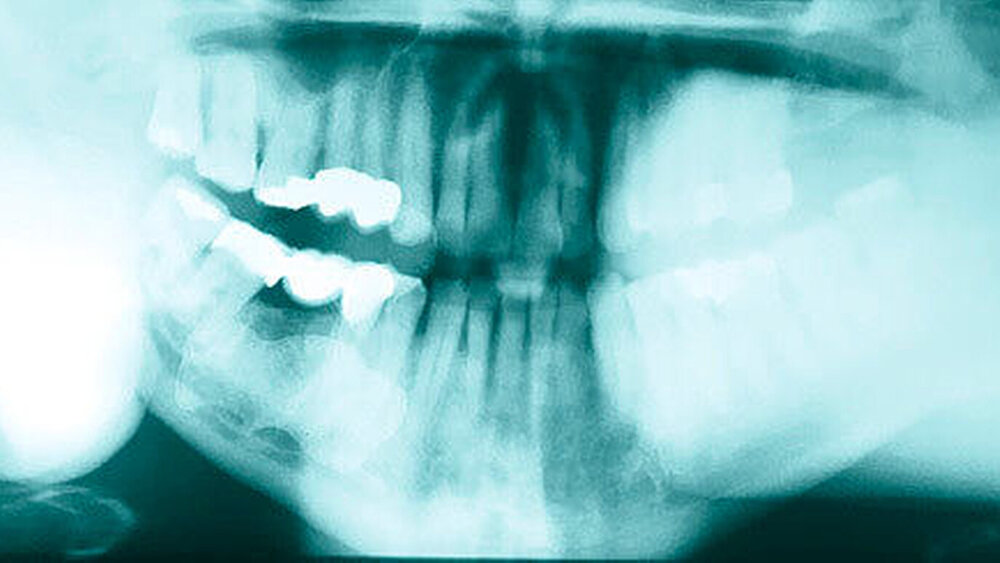

Im mitgebrachten alio loco erstellten Orthopantomogramm war eine gut abgrenzbare, ovale, homogene Verschattung zu sehen, welche sich im Bereich des rechten Kieferwinkels, in dorsaler und kranialer Richtung über diesen hinaus sowie im Bereich des aufsteigenden Unterkieferastes bis kaudal unter die Incisura semilunaris erstreckte (Abbildung 1). Computertomografisch war ausgehend von der medialseitigen Corticalis des Angulus mandibulae rechts eine irregulär, angedeutet rundlich konfigurierte, glatt begrenzte knöcherne Raumforderung von circa 4,4 x 3,3 x 4,7 cm Größe zu sehen (Abbildungen 2 und 3). Diese führte zu einer Verlagerung der Anatomie, insbesondere zu einer Vorwölbung der rechtsseitigen Oropharynxseitenwand (Abbildung 4). Es bestanden keine Hinweise auf eine knöcherne Destruktion oder auf eine Lagebeziehung zu einem Zahn.